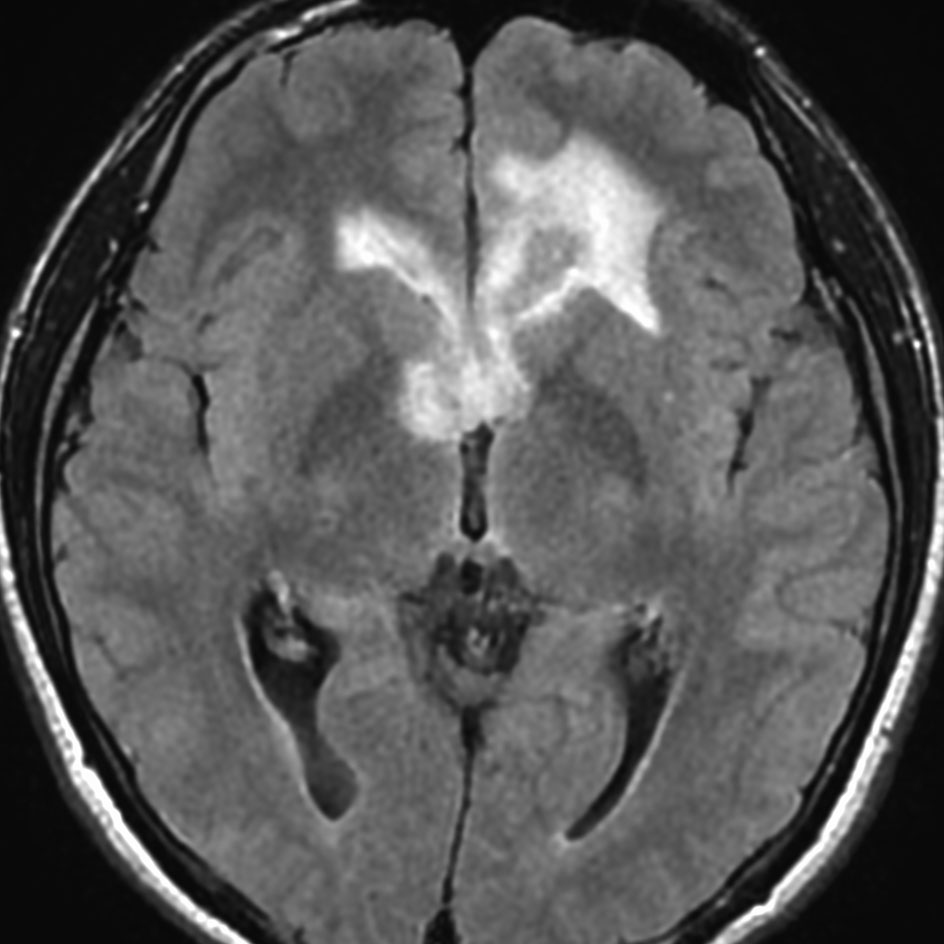

ジャーミノーマには好発部位というものがあります,神経下垂体,松果体,大脳基底核などですが,例外的な発生部位もあるので注意です。この例は,浸潤形態が脳室壁に沿う subependymal infiltrationという特徴からジャーミノーマと画像診断できるものです。

21歳男性で交通事故で偶然発見された両側前頭葉腫瘍です。

ガドリニウム増強では,前頭葉腫瘍というより,側脳室壁にベトベトくっついているような腫瘍です。germinoma特有のsubependymal infiltration像を示します。